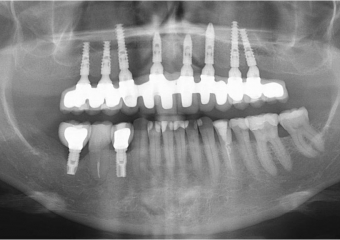

Raio x após prótese fixa provisória instalada

Raio x final